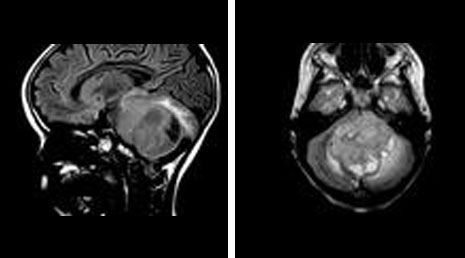

39. Medulloblastoma

48. Posterior fossa meningioma